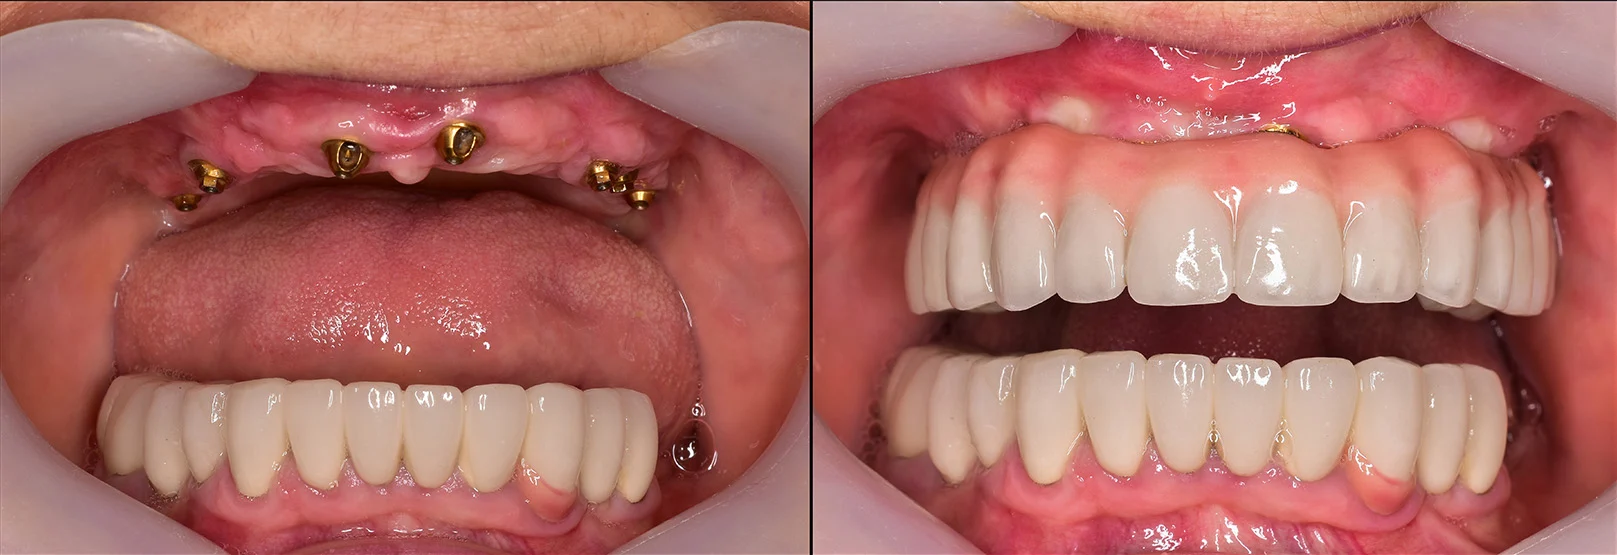

- All-on-4 implants: A full arch restoration technique that uses just four implants placed at specific angles to maximize existing bone without grafting.

- Zygomatic implants: These longer implants anchor into the cheekbone (zygoma) and are used when upper jaw bone is severely resorbed.

- Short or mini implants: Used in certain cases where standard-length implants can’t be supported but some bone remains.

These alternatives offer hope for patients with severe bone loss who wish to avoid or cannot undergo grafting procedures.